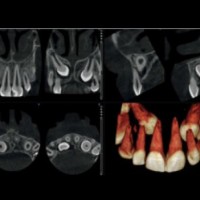

CT Vyšetrenie Poliklinika Mýtna Pro RTG

CT - Počítačová tomografia